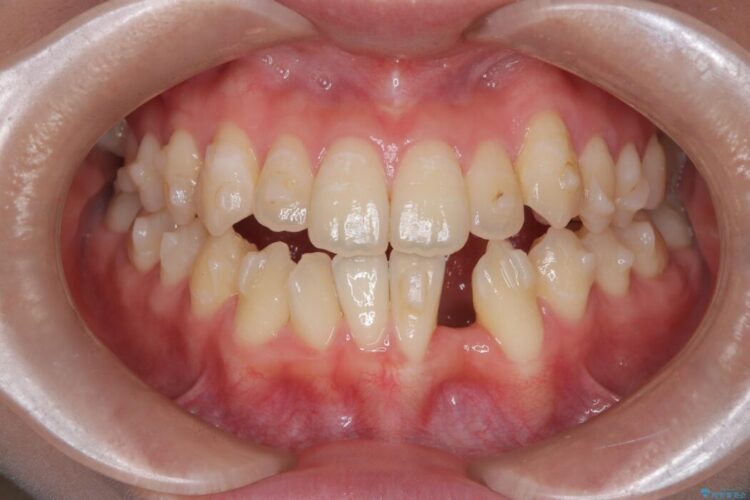

長期間の放置で骨が吸収した部位のインプラント治療

左下奥歯の抜歯後、長期間放置していたために、周囲の骨が吸収してしまいました。 特に垂直的な高さが不足しており、通常の術式ではインプラント埋入が難しい状態でした。

治療期間(治療回数):3ヶ月(2~5回) | 概算治療費:55万円